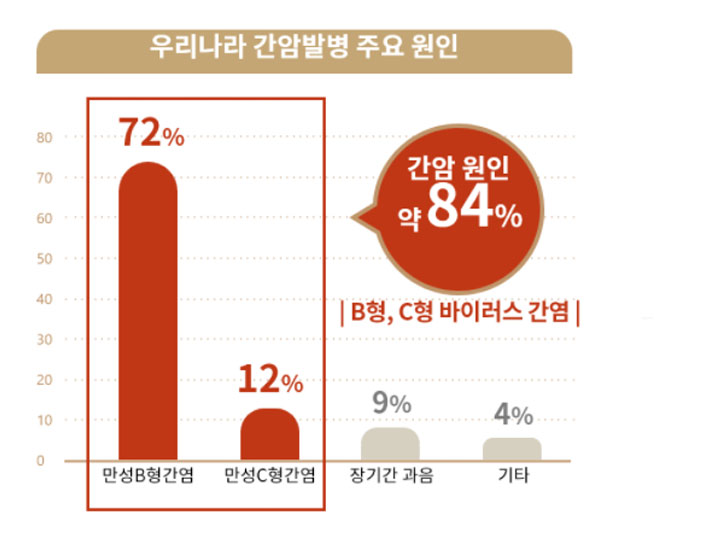

위험 요인

간암의 주원인은 B형과 C형 간염바이러스의 감염과 과도한 음주, 흡연 등 입니다. 최근의 한 통계에 따르면 간암 환자의 72%가 B형 간염바이러스(HBV, hepatitis B virus), 12%가 C형 간염바이러스(HCV, hepatitis C virus)의 영향을 받았으며, 9%가 알코올, 4%가 기타 원인과 연관이 있었습니다. 해마다 간경변증 환자의 1~5%에서 간암이 발생합니다. 간암은 간경변증이 심할수록, 연령이 높을수록 잘 생기고, 남자 환자가 많습니다

< 출처 대한간암학회 >